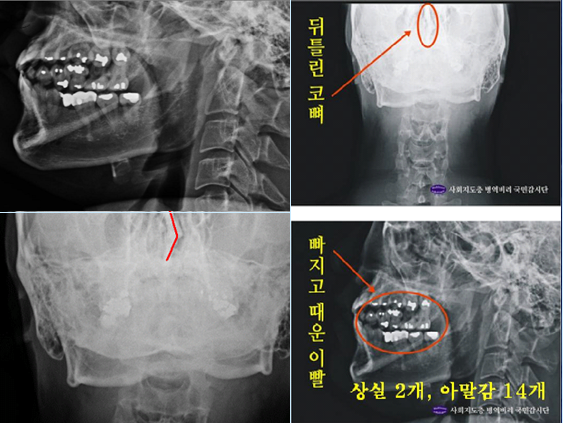

- ▲ 사병역비리국민감시단이 병역비리 의혹을 제기한 박주신 씨(박원순 서울시장 아들)의 치아 엑스레이 사진 ⓒ사회지도층병역비리감시단